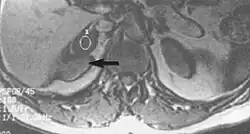

Metal artifacts occur at interfaces of tissues with different magnetic susceptibilities, which cause local magnetic fields to distort the external magnetic field. This distortion changes the precession frequency in the tissue leading to spatial mismapping of information. The degree of distortion depends on the type of metal (stainless steel having a greater distorting effect than titanium alloy), the type of interface (most striking effect at soft tissue-metal interfaces), pulse sequence and imaging parameters. Metal artifacts are caused by external ferromagnetics such as cobalt containing make-up, internal ferromagnetics such as surgical clips, spinal hardware and other orthopaedic devices, and in some cases, metallic objects swallowed by people with pica.[3] Manifestation of these artifacts is variable, including total signal loss, peripheral high signal and image distortion (Figs 3 and 4).[1] Reduction of these artifacts can be attempted by orientating the long axis of an implant or device parallel to the long axis of the external magnetic field, possible with mobile extremity imaging and an open magnet. Further methods used are choosing the appropriate frequency encoding direction, since metal artifacts are most pronounced in this direction, using smaller voxel sizes, fast imaging sequences, increased readout bandwidth and avoiding gradient-echo imaging when metal is present. A technique called MARS (metal artifact reduction sequence) applies an additional gradient, along the slice select gradient at the time the frequency encoding gradient is applied.